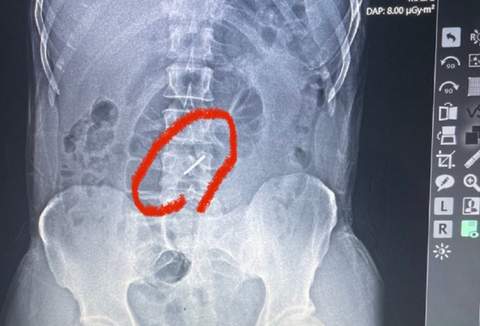

Бойца направили на рентген, результаты которого шокировали медиков.

"При обстреле элемент кассетной бомбы, так называемая "стрелка", попала в левое подреберье, сломала два позвонка в поясничном отделе позвоночника и застряла в позвоночнике", - рассказывает врач военно-полевого госпиталя, львовский сосудистый хирург Тарас Кобза.

"Стрелка" кассетной бомбы сломала 2 поясничных позвонка и застряла в позвоночнике (фото: zaxid.net)

Само ранение элементом кассетного боеприпаса произошло еще 13 июля, а к медикам пациент обратился лишь в начале августа.

"Он практически три недели воевал со сломанным хребтом", - отмечает Кобза.